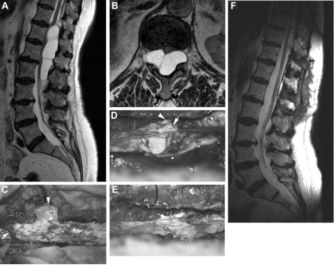

作者对硬脊膜病变提出新的系统分型:Ⅰ型,硬膜囊憩室;Ⅱ型,硬膜间夹层;Ⅲ型,硬膜梭形扩张(图1)。三者临床表现几乎类似,即缓慢进展的局部疼痛开始,然后出现神经根性症状和脊髓病表现,但代表着不同的疾病种类,诊断和治疗方法不同。

图1. 三类型硬脊膜病变的特点。硬膜囊憩室(Ⅰ型)、硬膜间夹层(Ⅱ型)、硬膜梭形扩张(Ⅲ型)。三类型均可出现局部疼痛、神经根和脊髓病症状。Ⅱ型和Ⅲ型还因为慢性的脑脊液流失而导致低颅压综合征和中枢神经系统铁质沉积症的表现。